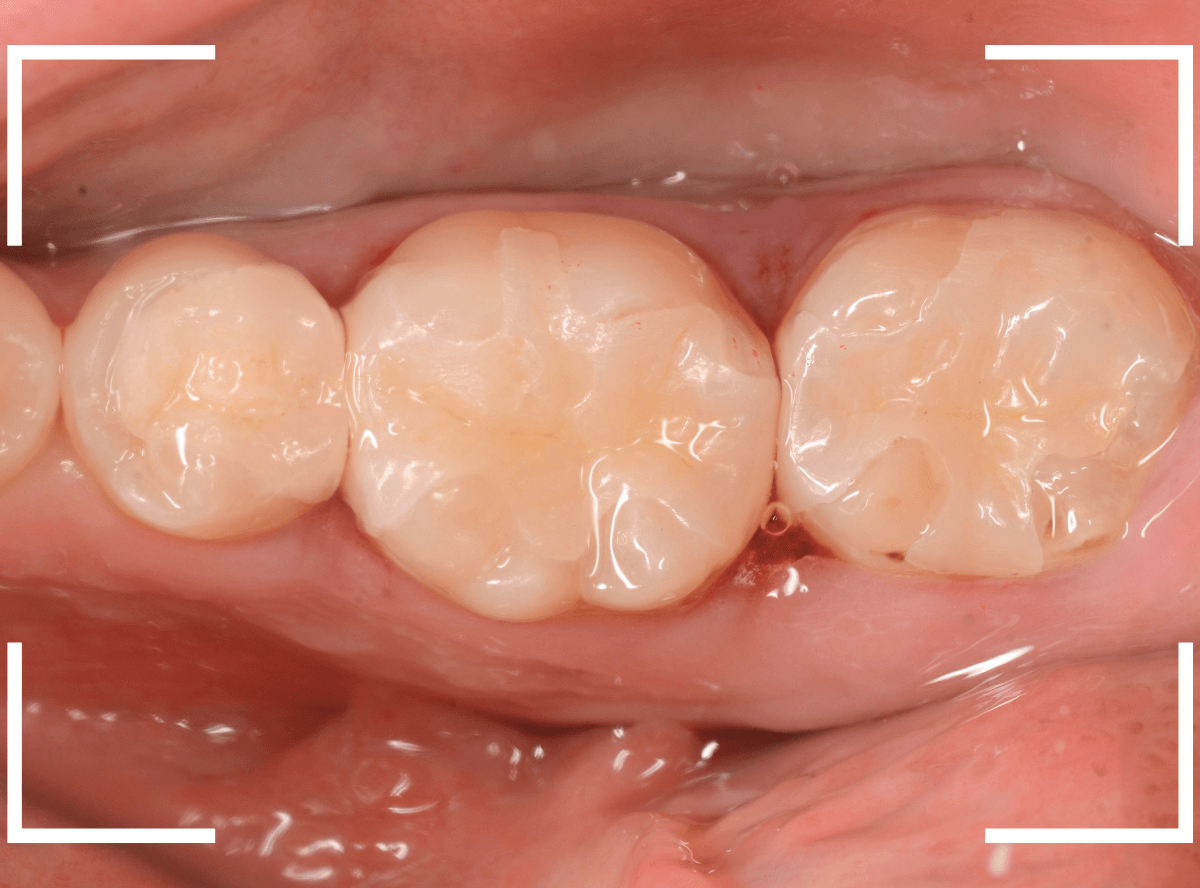

全く染色されなくなりました。

これで全ての虫歯を除去したことになります。